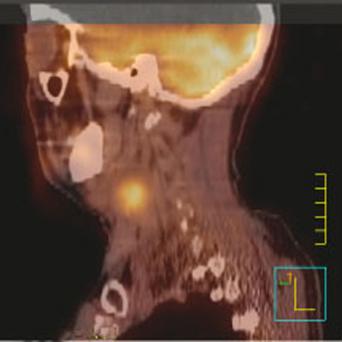

Les patients âgés représentent plus de la moitié des cas incidents de cancer car la population française vieillit et l’oncogenèse et la sénescence partagent de nombreux mécanismes biologiques s’entraînant mutuellement. Leur prise en charge pose donc de nombreux défis – d’autant que le cancer et les...

- Particularités des traitements médicaux antitumoraux chez le sujet âgé